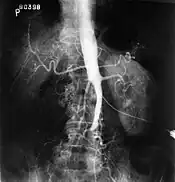

El síndrome de Leriche o enfermedad oclusiva aortoiliaca es una condición patológica que consiste en la oclusión ateroesclerótica que compromete la aorta abdominal y/o las arterias ilíacas comunes.

Tríada diagnóstica: pulsos femorales ausentes o disminuidos, claudicación o dolor al caminar en miembros inferiores (cadera y pantorrillas) y disfunción eréctil.

Bypass vascular o puente con injerto aortobifemoral es el tratamiento definitivo. La prevención secundaria se hace con la supresión total del tabaco. En caso de que se presente gangrena de una extremidad, se debe amputar.